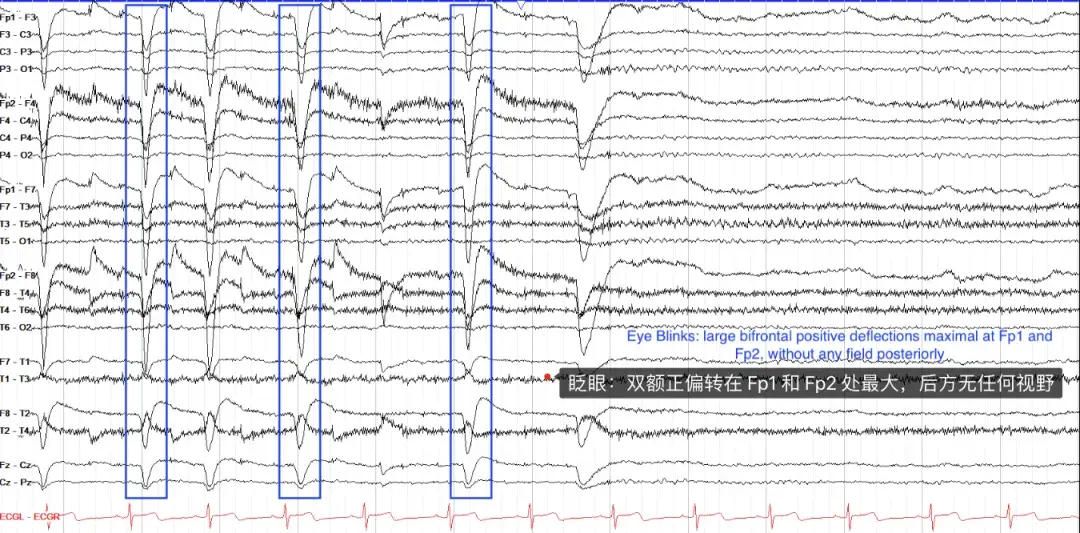

① 眨眼伪影(Blink artifacts)

眨眼是会看到的最常见的伪影之一,其特征是双额区域的振幅非常高的负波形。它们的出现是由于贝尔现象。

眼睛的角膜带正电,视网膜带负电;当你眨眼时,眼睛会稍微上翻,角膜会靠近额电极 Fp1 和 Fp2,从而看到脑电图上反射的正信号。

眨眼实际上应该只在额叶导联中可见,而后部区域没有任何视野。闭眼时会看到类似的波形,而睁眼时会看到一种相反的波形,即大的双额负电荷。眨眼是正常清醒脑电图的一个关键组成部分。注意,不要将它们误认为是额叶棘波和前波,或前部主导的广义棘波和波。